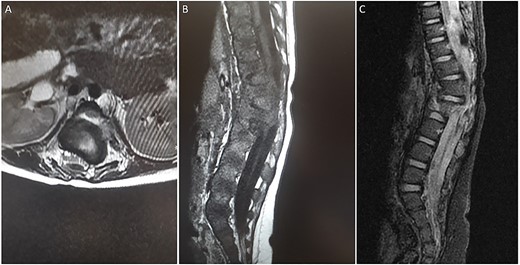

Radiological imaging

A spine radiograph and CT scan (Figs 1 and 2) revealed a three-column fracture of T12-L1 and an L2 body fracture. A multiplanar and multisequential MR images (Fig. 3) of the whole spine were performed utilizing trauma protocol. The images demonstrated narrowing of the spinal canal at the level of thoracolumbar junction secondary to multilevel fractures along with myelomalacia changes involving the lower thoracic cord and conus medullaris. Additionally, the images showed an evidence of kyphosis measuring 47° at the fracture site.

(A) axial T2-weighted MRI. (B) Sagittal T1-weighted MRI (C) Sagittal STIR MRI. (A-C) There are multiple fractures involving the lower thoracic and upper lumbar spine with involvement of the posterior columns and narrowing of the spinal canal. There is a large extramedullary lesion likely representing a small subdural hematoma.